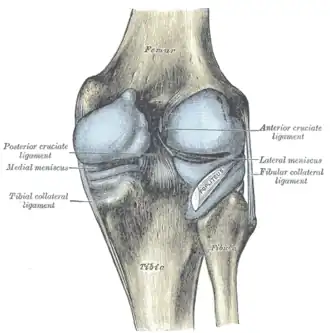

Menisci

The articular disks of the knee-joint are called menisci because they only partly divide the joint space.[10]: 26 These two disks, the medial meniscus and the lateral meniscus, consist of connective tissue with extensive collagen fibers containing cartilage-like cells. Strong fibers run along the menisci from one attachment to the other, while weaker radial fibers are interlaced with the former. The menisci are flattened at the center of the knee joint, fused with the synovial membrane laterally, and can move over the tibial surface.[10]: 208 [18] The upper and lower surfaces of the menisci are free. Each meniscus has anterior and posterior horns that meet in the intercondylar area of the tibia.[13]

Medial meniscus is bigger, less curved, and thinner. Its posterior horn is thicker (14mm) than the anterior horn (6mm).[13]

The lateral meniscus is smaller, more curved (nearly circular), and has more uniform thickness than medial meniscus (10mm). The lateral meniscus is less attached to the joint capsule, because its posterolateral surface is grooved by the popliteus tendon, separating the meniscus from the capsule. The popliteus tendon is not attached to the lateral meniscus.[13]

Ligaments

The ligaments surrounding the knee joint offer stability by limiting movements and, together with the menisci and several bursae, protect the articular capsule.[19]

Intracapsular

The knee is stabilized by a pair of cruciate ligaments. These ligaments are both extrasynovial, intracapsular ligaments.[20] The anterior cruciate ligament (ACL) stretches from the lateral condyle of femur to the anterior intercondylar area.[13] The ACL prevents the tibia from being pushed too far anterior relative to the femur.[13] It is often torn during twisting or bending of the knee.[21] The posterior cruciate ligament (PCL) stretches from medial condyle of femur to the posterior intercondylar area. This ligament prevents posterior displacement of the tibia relative to the femur.[13] Injury to this ligament is uncommon but can occur as a direct result of forced trauma to the ligament.

The transverse ligament stretches from the lateral meniscus to the medial meniscus. It passes in front of the menisci. It is divided into several strips in 10% of cases.[10]: 208 The two menisci are attached to each other anteriorly by the ligament.[22] The posterior (of Wrisberg) and anterior meniscofemoral ligaments (of Humphrey) stretch from the posterior horn of the lateral meniscus to the medial femoral condyle. They pass anterior and posterior to the posterior cruciate ligament respectively.[13][10]: 208 The meniscotibial ligaments (or "coronary") stretches from inferior edges of the menisci to the periphery of the tibial plateaus.

Cruciate ligaments -

Left knee-joint from behind, showing interior ligaments. -